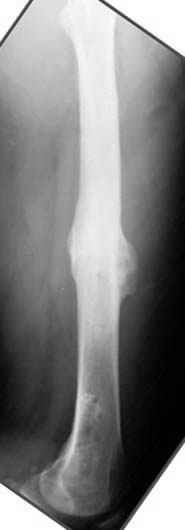

На рисунке N1 предоперационный план лечения ложного сустава шейки бедра- линия ложного сустава, угол и направление введения импланта, клиновидная остеотомия в градусах и миллиметрах, второй снимок после коррекции, расчет, на сколько удлиняется конечность и размеры импланта;

N3 рисунок окончательный снимок, после операции моя рентгенограмма должен выглядеть примерно как эта картина. На N4 снимке клин перед удалением; N5 послеоперации 3 нед.; N6 окончательная рентгенограмма.

пластическая модель; и коррекция бедра аппаратом Илизарова.